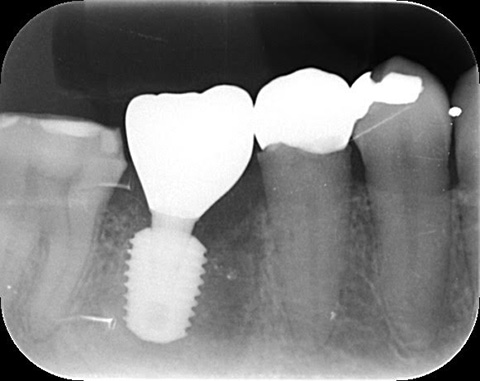

オペから2ヶ月後のレントゲン写真。

インプラント周囲に骨が出来てきていることがわかります。

レントゲンで適合精度も確認します。